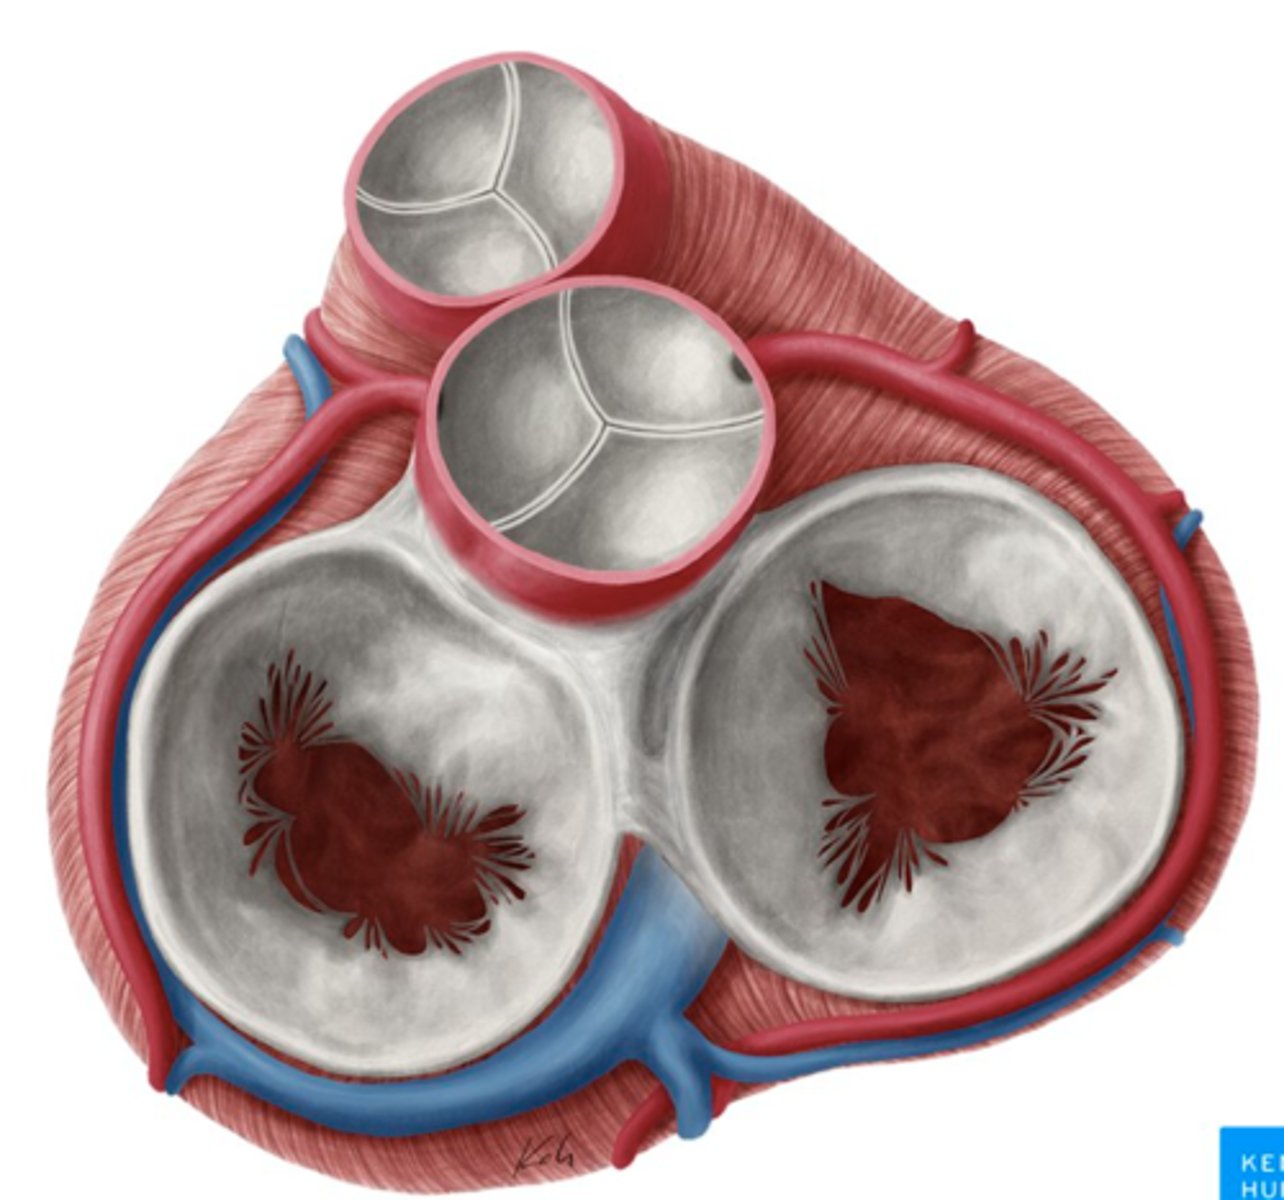

AXIAL VIEW OF THE HEART

What are the 3 cusps of the tricuspid valve?

Anterior

Posterior

Septal

What are the positions of the pulmonary valve cusps?

Anterior

Right

Left

What is the valve in the AV left canal?

. Mitral valve

2 cusps (anterior and posterior) and 2 associated papillary muscles

What are the 3 parts of the aortic valve?

3 semilunar cusps

posterior

right

left

What are the four valves in the heart?

Tricuspid

Mitral or bicuspid

Pulmonary

Aortic

What are other functions of the rings in the cardiac skeleton?

maintain the shape of the openings between the heart's chambers

insertion site for the cusps of the valves and muscular heart tissue.

What are the components of the cardiac skeleton?

. pulmonary ring,

. aortic ring

. AV rings

RINGS ARE IN THE SAME PLANE AROUND THE VALVES